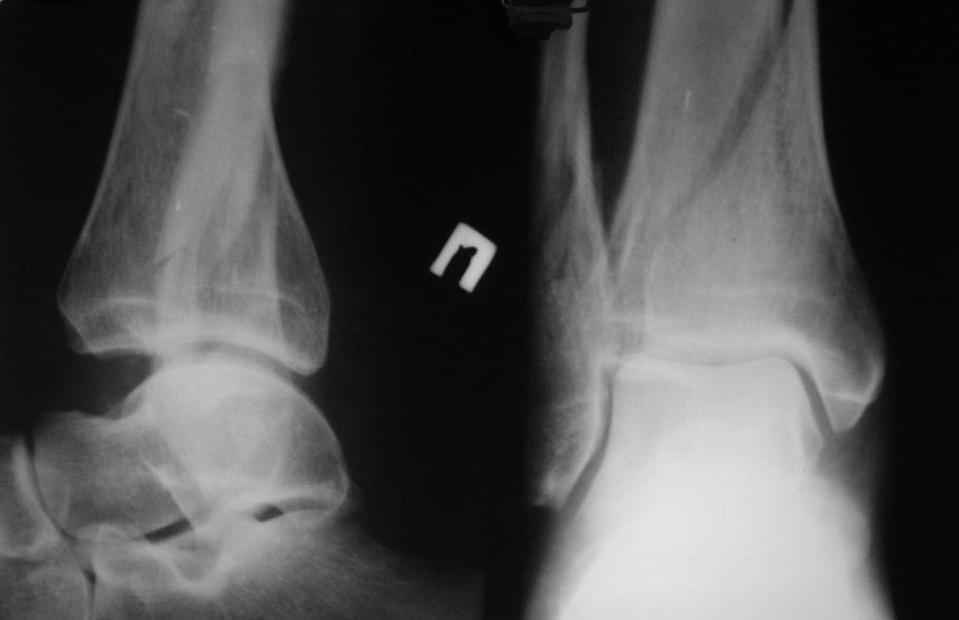

Re: перелом пилона. тактика лечения

прошу прощения за то, что забыл приложить снимки